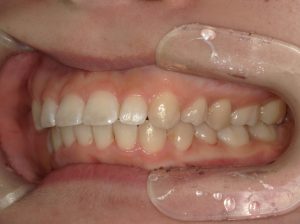

治療前→治療後(右側方)

治療前→治療後(左側方)

左側の第二小臼歯部と第二大臼歯部の鋏状咬合(ハサミのようにすれ違っているかみ合わせ)を改善しました。